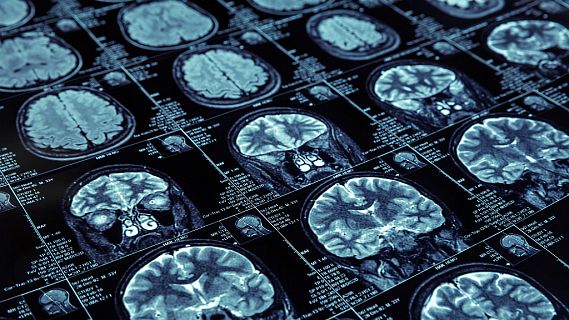

Vamos a descubrir los síntomas de un ictus y quién lo provoca, y para ello nos hemos acercado al trabajo que desarrollla la Federación Española de Ictus. Para conocer más detalles sobre esta patologia y como prevenirla, hemos entrevistado a la presidente de la Federación, Carmen Aleix.